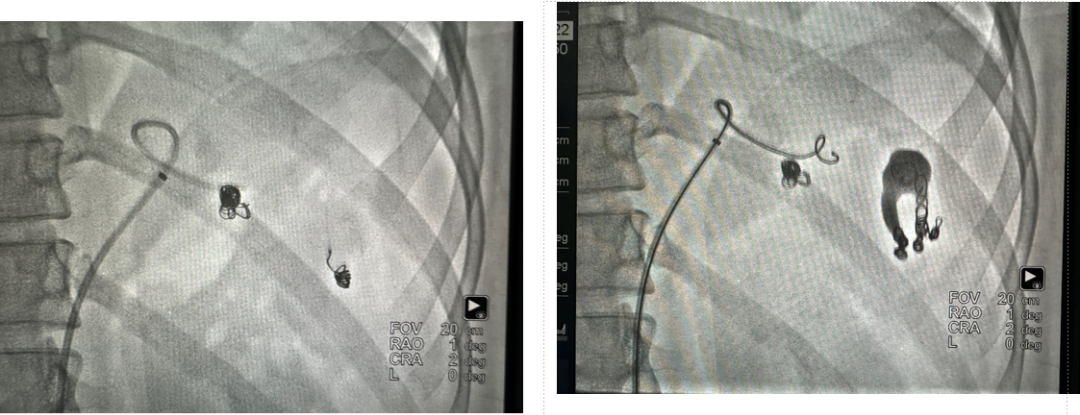

病例5 多发动脉瘤分支+主干栓塞

图为:分支栓塞

图为:主干栓塞最后造影